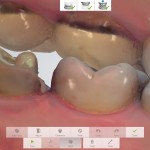

3shapeB4T director, Dr. Sorensen is the PI of this project working with Drs. Chen and Sadr on single tooth CAD/CAM restoration and new adhesive resin cement. The clinical study focuses on new FDA approved materials that utilize a dual-curing composite resin cement in combination with a light-cured single component dental adhesive for cementation of posterior ceramic restorations. The study is currently recruiting patients.